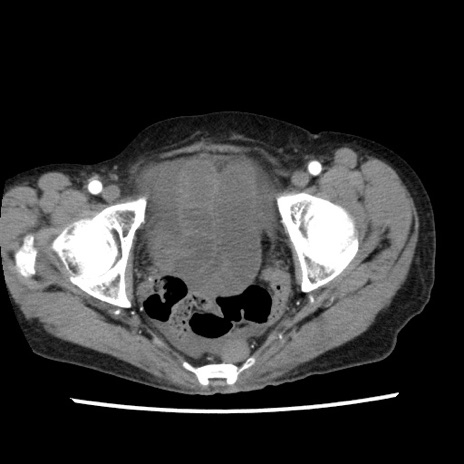

症例1(横断像)

【症例】80歳代女性

【主訴】腹痛

【現病歴】8時間前から腹痛あり来院。

【既往歴】糖尿病、脂質異常症、子宮体癌にて子宮全摘術

【身体所見】意識清明・会話良好だが腹痛で苦悶様、全腹部にわたって反跳痛と圧痛あり

【データ】WBC 13600、CRP 0.14、LDH 224、CK 90